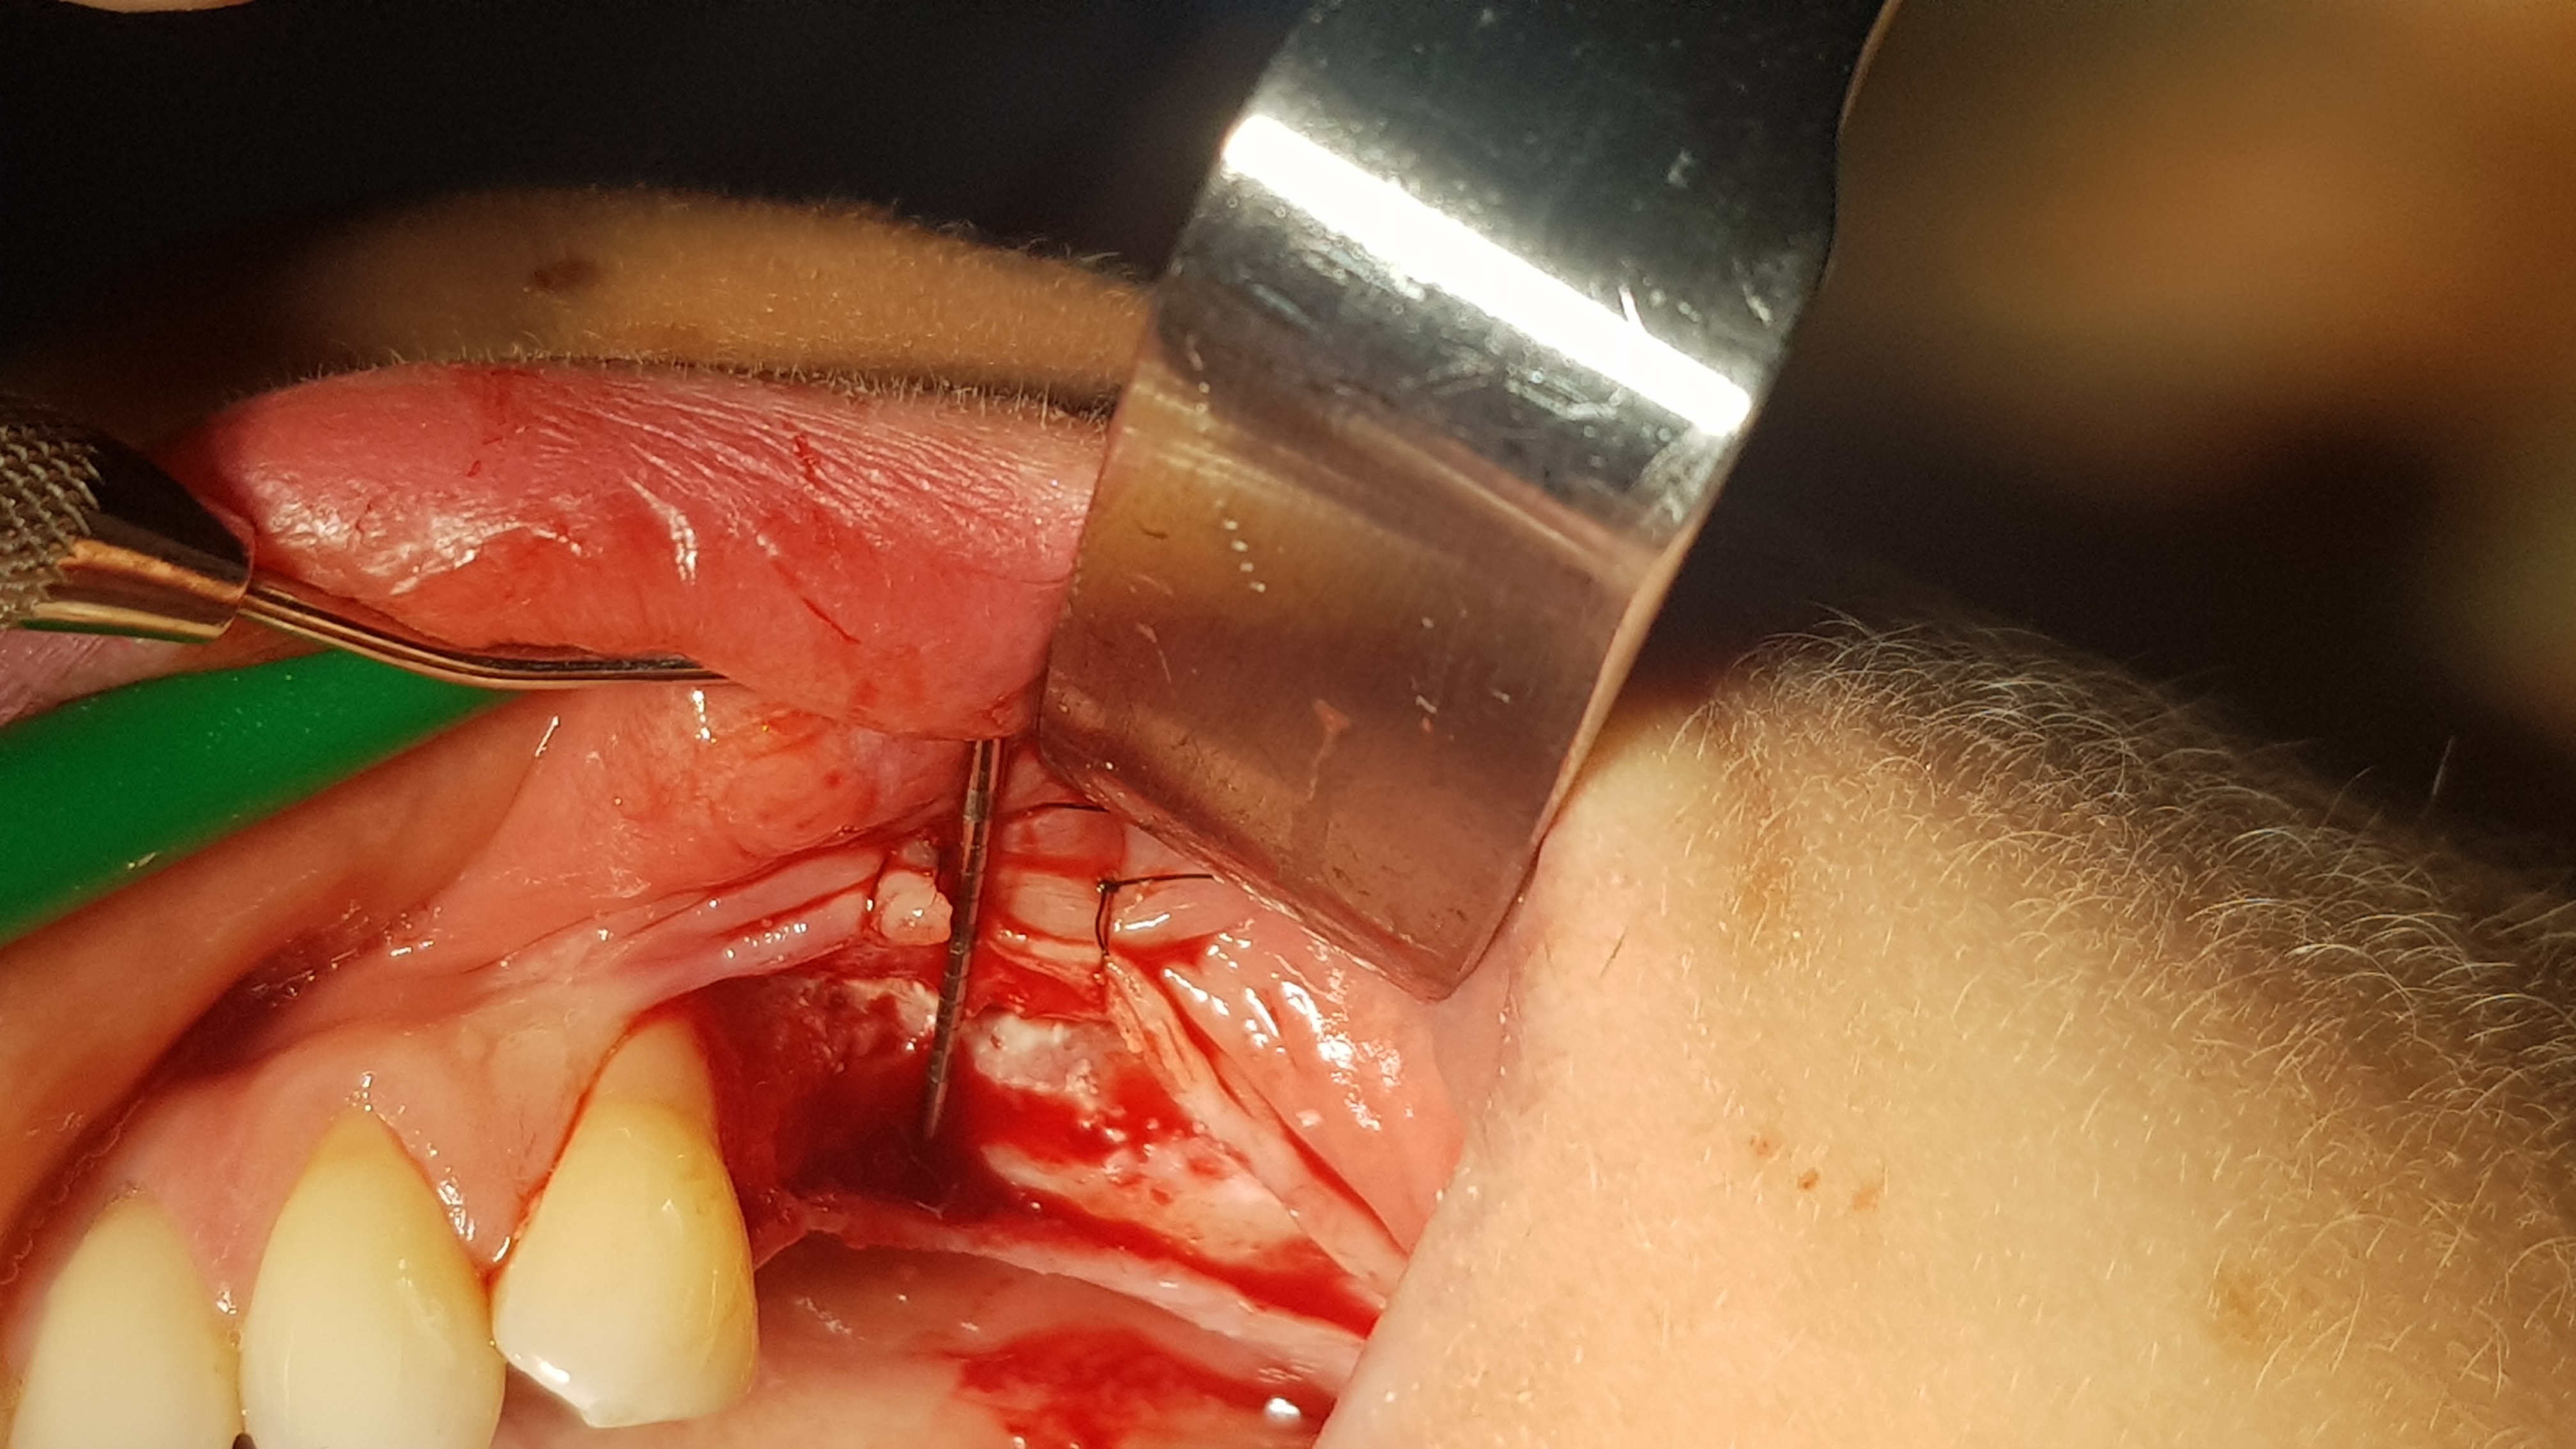

Brzegi rany zbliżono na odległość około 5 mm i zaopatrzono szwami (polidioksanon 4-0, igła okrągła kłująca, długość 16 mm, profil ½ koła). Po okresie 14 dni uzyskano ziarninowanie tkanki miękkiej. Drugi etap wykonano po 3 miesiącach. Dostęp do wyrostka wykonano w sposób typowy, jednym cięciem poziomym rozpoczynając na jego szczycie od okolicy 47, przedłużając do okolicy zęba 44 a następnie do przodu przez dziąsło zbite 44 i kończąc cięciem pionowym w połowie szerokości korony 44. Po odpreparowaniu tkanek miękkich uwidoczniono kość części zębodołowej, której powierzchnię poddano usunięciu pozostałości tkanek miękkich przy użyciu dedykowanych przez producenta wierteł z nasypem diamentowym.

Ryc. 6. Wytworzenie płata kątowego. Ryc. 7. Dekortykacja blaszki korowej.

Następnie wykonano otwory trepanacyjne w blaszce korowej kości o średnicy około 3 mm dochodząc do kości gąbczastej (ryc. 7). Taka średnica jest zalecana przez producenta dla lepszej retencji i utrzymania kształtu cementu regeneracyjnego w takim ubytku. Następnie po aktywacji umieszczono i uformowano cement na przygotowanej powierzchni kości (2 cm3) (ryc. 8).

Ryc 8. Uformowanie cementu na powierzchni wyrostka.   Ryc 9. Zaopatrzenie rany.

Kształt opracowano ręcznie przy użyciu raspatora i sterylnych gazików 5/5 cm. Następnie ranę przykryto płatem bez podcinania okostnej, a jedynie rozciągając go o kilka milimetrów dzięki wykorzystaniu pewnej elastyczności błony śluzowej. Ranę zaopatrzono szwami (polidioksanon 4-0, igła okrągła kłująca, długość 16 mm, profil ½ koła oraz nylon 5-0, igła odwrotnie tnąca, długość 12 mm, profil 3/8 koła) (ryc. 9). Pacjentka po zabiegu stosowała standardową antybiotykoterapię doustną (Amoksycylina 1.0 g co 12h 7 dni) oraz miejscowo płukanie jamy ustnej roztworem chlorcheksydyny. Rana goiła się prawidłowo, szwy usunięto w 10 dobie po zabiegu oraz wykonano kontrolne projekcje rtg, które wykazały prawidłowe utrzymanie cementu na wyrostku (ryc. 6-12).